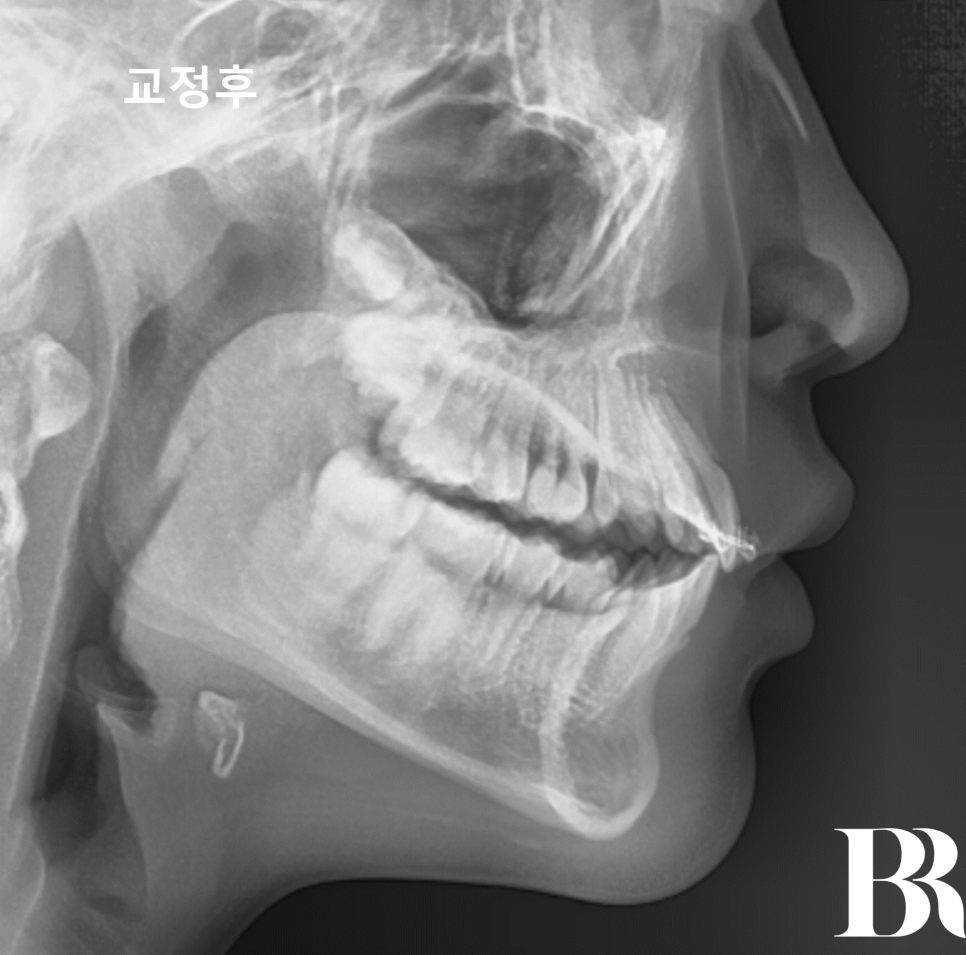

1년 4개월 간 이루어진

턱교정치료가 끝났습니다.

아래턱이 이쁘게 나왔고

윗니와 아랫니의 앞뒤 차이가

정상 범위 내로 줄어들었습니다.

발치교정을 요하지 않는

상태로 만들었습니다^^